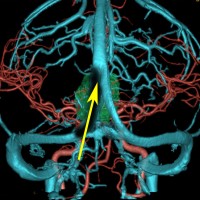

小さな松果体奇形腫です。

OTAでこの奇形腫を見ようとする場合に,テントを静脈洞交会の低い位置まで切断しなければ,直静脈洞の横から松果体部をみることはできません。また,黄色の矢印の方向に視野が入るので,まず最初に邪魔になるのは小脳上極です。上小脳層を左右ともに十分剥離すると,小脳が可動化して,その向こうに,precentral cerebellar veinが見えます。このveinをガレン大静脈への流入部から小脳前面に沿って剥離していくと,小脳上極がさらに可動化して松果体への視野が開ます。

松果体腫瘍の手術では,中脳背面を見る必要があります。特に上丘とそれに連続する後交連 posterior commissureを十分に観察するために周囲組織の剥離を行います。具体的には迂回槽と下丘の周囲のクモ膜組織を剥離します。対側中脳と迂回槽を見る時に妨げになるのが,緑の矢印で示した直静脈洞です。テントが長く切断してあって直静脈洞が大脳鎌と一緒に動かせると対側を見るのがとても簡単になります。